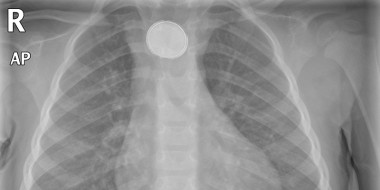

Een gerichte anamnese en een algemeen lichamelijk onderzoek vormen de hoeksteen voor het beleid bij kinderen die een vreemd voorwerp hebben ingeslikt. (Spoed)verwijzing naar de tweede lijn is noodzakelijk bij patiënten die ABCDE-instabiel zijn, patiënten die tekenen van ontsteking (koorts)…